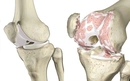

Diz kapağı ameliyatı, diz ekleminde meydana gelen çeşitli rahatsızlıkların tedavisinde uygulanan cerrahi bir müdahaledir. Bu tür ameliyatlar, genellikle diz kapağının yerinden çıkması, yaralanmalar, artrit veya diğer diz problemleri nedeniyle gerçekleştirilir. Ancak, bu tür bir cerrahinin kendi içinde belirli riskler ve sonrasında göz önünde bulundurulması gereken durumlar söz konusudur. Diz Kapağı Ameliyatının RiskleriDiz kapağı ameliyatı, her cerrahi işlemde olduğu gibi bazı riskler taşır. Bu riskler arasında şunlar yer almaktadır:

Uzun Dönem Sonuçlar ve İyileşme SüreciDiz kapağı ameliyatının uzun dönem sonuçları, hastanın genel sağlık durumu, yaş, fiziksel aktivite düzeyi ve rehabilitasyon sürecine bağlı olarak değişkenlik göstermektedir. Genellikle hastalar, ameliyat sonrası birkaç hafta içerisinde günlük aktivitelerine dönebilir. Ancak, tam iyileşme süreci birkaç ay sürebilir. SonuçDiz kapağı ameliyatı, birçok hastada yaşam kalitesini artırma potansiyeline sahip önemli bir cerrahi müdahaledir. Ancak, yaşanabilecek riskler ve ameliyat sonrası bakım süreci göz önünde bulundurulmalıdır. Hastaların, cerrahiden önce ve sonra doktorlarıyla düzenli iletişimde kalarak en iyi sonuçları elde etmeleri hedeflenmelidir. |